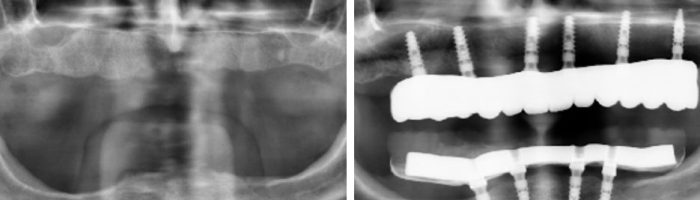

La cirugía ósea regenerativa e implantológica es otro tipo de cirugía bucal. Este tipo de cirugía se realiza cuando el paciente tiene atrofia ósea o falta de hueso, para posteriormente poder colocar implantes dentales.

La cirugía bucal en Valencia también incluye procedimientos como la cirugía de la encía para la estética de la sonrisa, los implantes dentales y la cirugía regenerativa ósea o reconstructiva en casos de falta de hueso para permitir la posterior colocación de implantes dentales.